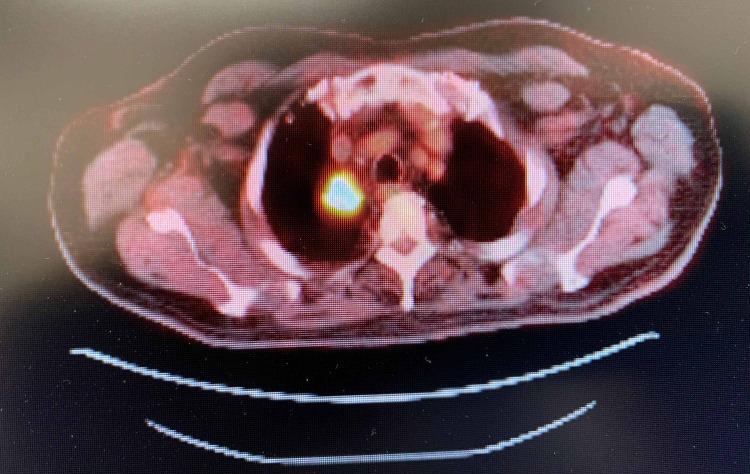

Pembrolizumab is an immune checkpoint inhibitor approved for use in many cancer types such as non-small cell lung cancer (NSCLC), metastatic melanoma, head and neck cancers, hepatocellular carcinoma, and renal cell carcinoma. There are many reported cases of patients on immunotherapy who have discontinued treatment due to the development of immune-related adverse effects (irAE). Recognition of the histopathologic patterns of dermatologic toxicities due to immunotherapy will become increasingly important for ensuring appropriate management and optimal patient care. Here, we present a case of a 72-year-old man with metastatic carcinoma of unknown primary origin treated with pembrolizumab who developed an immune-related cutaneous adverse event (ircAE) in the form of lichenoid dermatitis.

帕博利珠单抗是一种免疫检查点抑制剂,已被批准用于多种癌症类型,如非小细胞肺癌(NSCLC)、转移性黑色素瘤、头颈癌、肝细胞癌和肾细胞癌。有许多关于接受免疫治疗的患者因出现免疫相关不良反应(irAE)而停药的报道病例。认识免疫治疗引起的皮肤毒性的组织病理学模式对于确保适当的管理和最佳的患者护理将变得越来越重要。在此,我们报告一例72岁男性患者,其原发灶不明的转移性癌接受帕博利珠单抗治疗后出现了苔藓样皮炎形式的免疫相关皮肤不良事件(ircAE)。